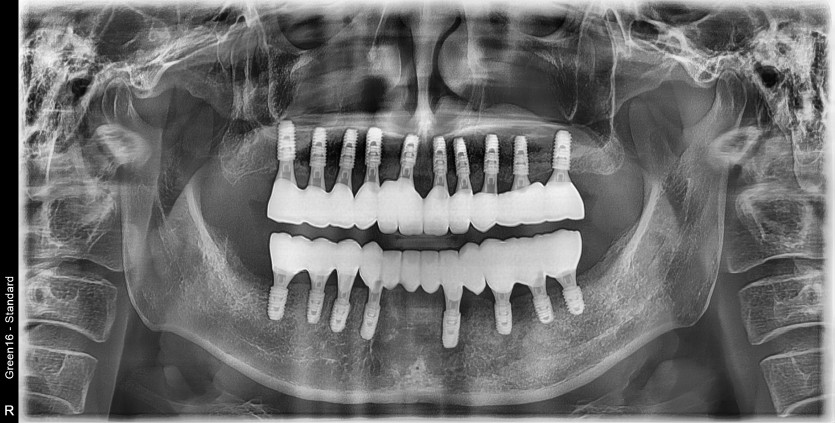

전체 임플란트 증례입니다.

18개의 임플란트로 완성하였습니다.